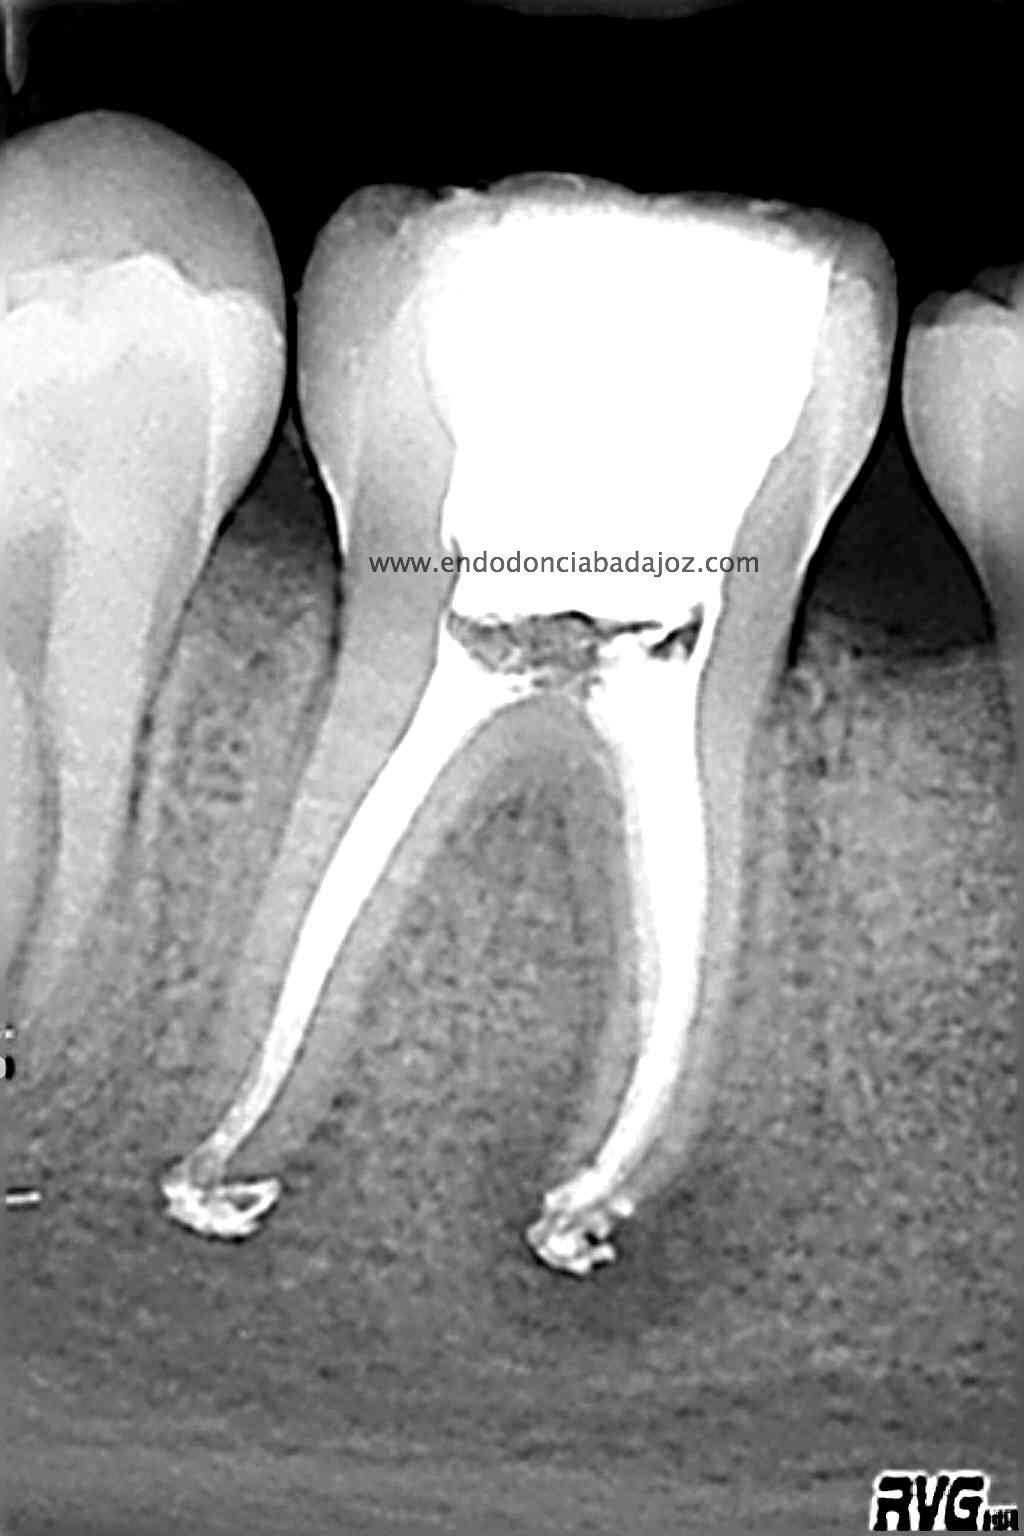

Cuando tratamos a niños, tenemos que entender que en muchas ocasiones los conductos no se han cerrado formando sistemas de conductos muy difíciles de limpiar tanto química como mecánicamente. Es este caso, presentaba un istmo mesial acintado que lo tratamos como si tuviese varios conductos. Colocamos H de Ca, soy ,en ciertos casos, un defensor del medicamento intraconductos, con lo que lo hicimos en  dos sesiones.

Se trata de un caso similar a este otro visto desde oclusal, observamos un istmo en la raiz mesial que tratamos como si fuesen varios conductos.

Una vez que hemos limpiado los conductos con un sistema de instrumentación  Protaper en combinación con limas K3. Pasamos a obturar los mismos con una técnica de condensación vertical de ola contínua de Buchanan y un backfilling con la gutapercha inyectada de la pistola ObturaII. Tomamos varias proyecciones, orto-mesio-distal

Con estas tres proyecciones nos quedamos mucho más tranquilos y seguros de un buen sellado hermético y tridimensional des sistema de conductos de esta pieza.